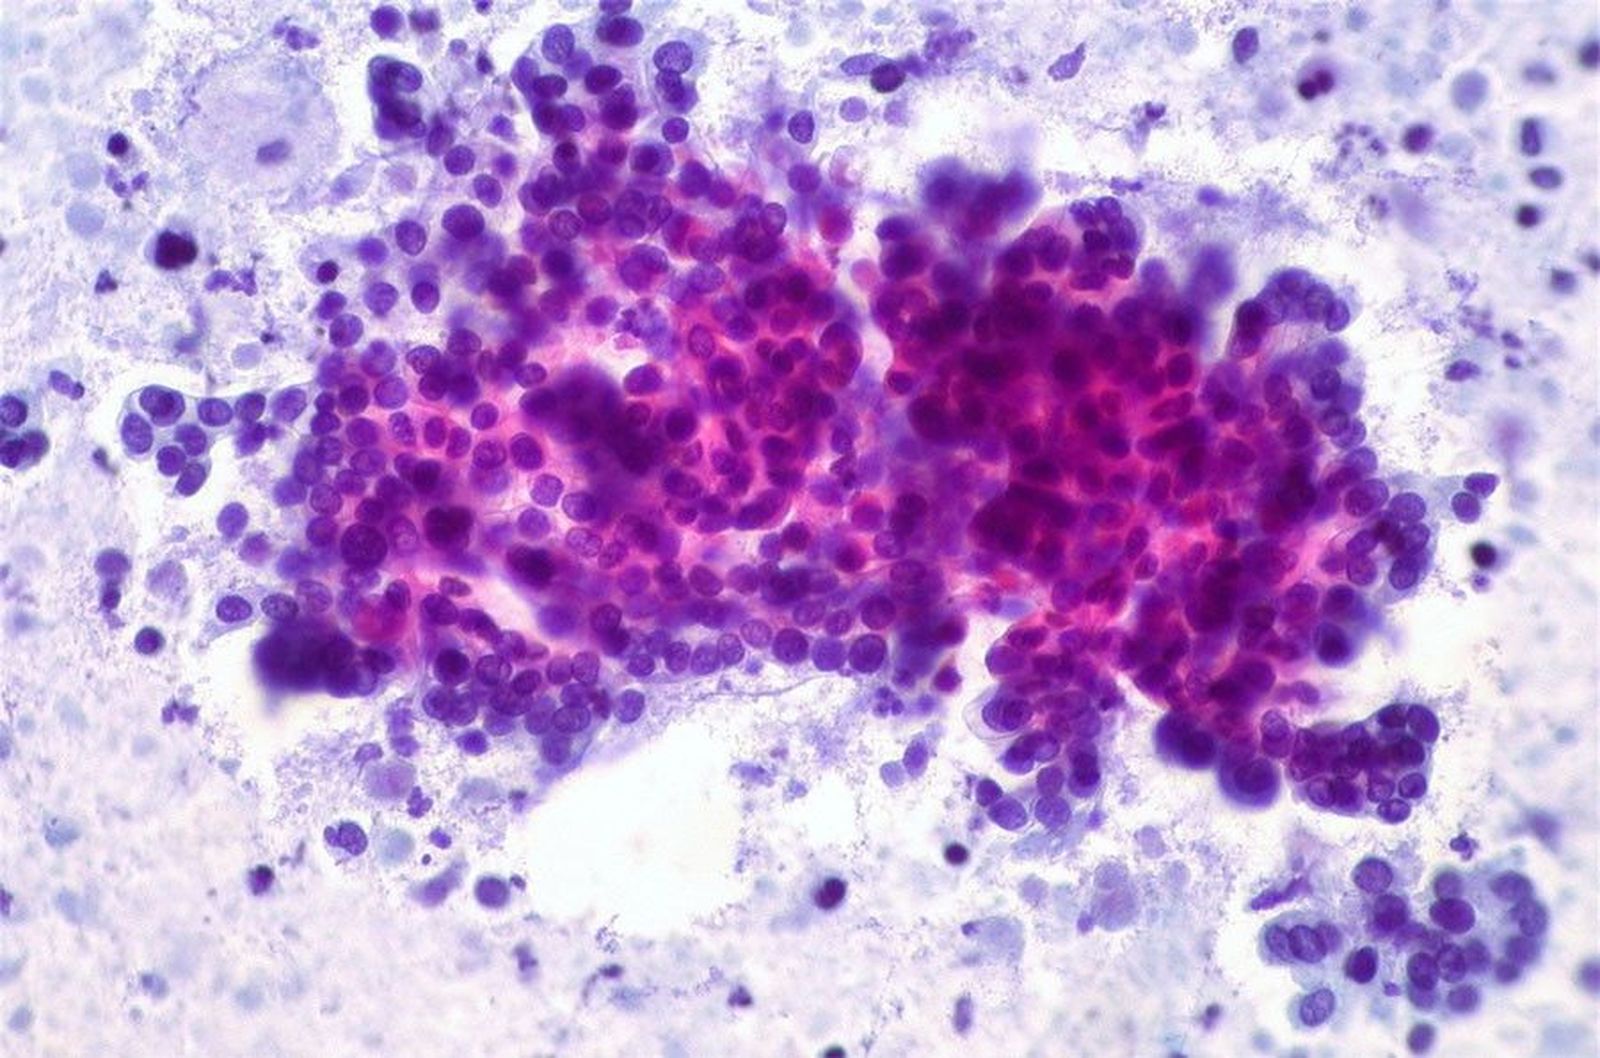

Cancer pancreas

Investigadores del Grupo de Oncología Experimental del Centro Nacional de Investigaciones Oncológicas (CNIO), liderados por el doctor Mariano Barbacid, han logrado eliminar en un modelo experimental de ratones el adenocarcinoma ductal de páncreas (ADP), una de las formas más agresivas de tumor y de las que más resistencia presenta a los tratamientos actuales.